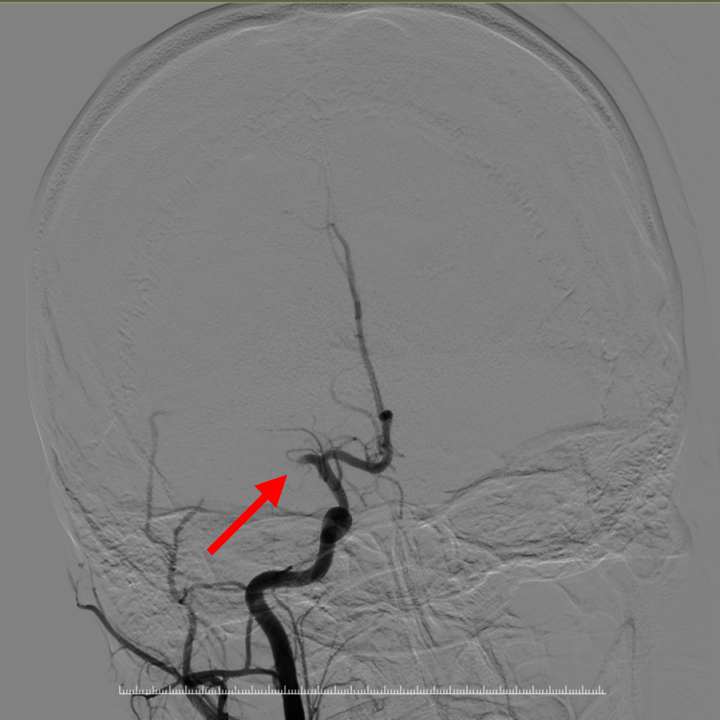

图1 图2

图1.DSA证实右侧大脑中动脉闭塞;图2.血栓抽吸术后右侧大脑中动脉复通

当天上午11点32分,手术顺利完成,小美神志转清,左上肢可以抬举,复查颅脑CT后送入神经内科二区进行后续治疗。